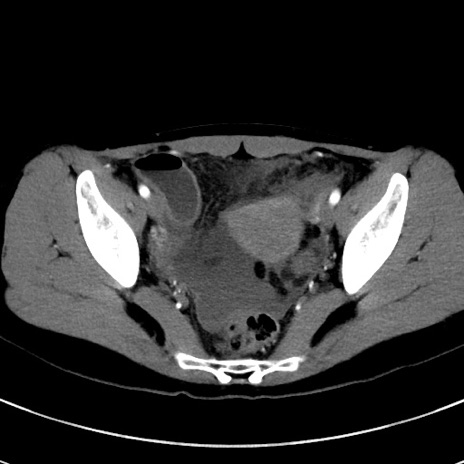

冠状断像

【症例】20歳代女性

【主訴】嘔吐、下腹部痛

【現病歴】昨日夕食後に嘔吐し下腹部痛が出現。本日になっても嘔吐持続し改善しないため来院。

【身体所見】意識清明、BT 37.2℃、BP 108/67mmHg、腹部:平坦、やや硬、下腹部正中から右にかけて圧痛あり、反跳痛軽度あり、tapping pain(+)。

【データ】WBC 13600、CRP 14.94